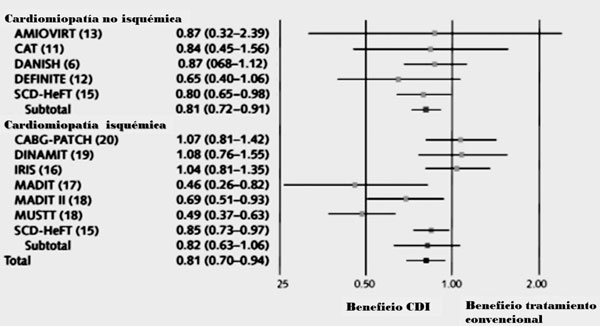

2. Cardiodesfibrilador implantable para prevención primaria de muerte súbita en la insuficiencia cardíaca

Las arritmias ventriculares malignas son la causa de la gran mayoría de estas MS. Numerosos ensayos clínicos randomizados, que se comentarán más adelante, han demostrado que el CDI es la terapéutica más eficaz para reducir la MS dado que es capaz de detectar y terminar con las arritmias ventriculares. Inicialmente se estableció su beneficio, en términos de sobrevida, para pacientes que experimentaron y sobrevivieron a una arritmia ventricular sintomática o a un paro cardiorrespiratorio (prevención secundaria)2), (3), (4. En los últimos 15 años se ha demostrado, además, que este beneficio se extiende a la prevención primaria, es decir, a tratar el primer evento potencialmente fatal (Figura 1). Numerosos estudios avalan la indicación de implante profiláctico de CDI para subgrupos de alto riesgo de presentar arritmias ventriculares malignas. Es muy importante estratificar correctamente el riesgo y sopesarlo con el de infección, choques inapropiados, calidad de vida, mortalidad asociada al dispositivo, así como también costos y comorbilidades para poder determinar la población en que el implante de CDI tendrá impacto en la disminución de la mortalidad total y no solo arrítmica. El mayor conocimiento de la historia natural de la enfermedad, de sus mecanismos fisiopatológicos, así como de los resultados de estudios recientemente publicados determinan que sea necesario analizar por separado el rol del CDI en prevención primaria en la cardiomiopatía isquémica (CMI) y en la cardiomiopatía no isquémica (CMNI).

2.1. CDI en la prevención primaria de muerte súbita en cardiomiopatía isquémica

Los primeros estudios del tema investigaron el beneficio del CDI en pacientes con CMI y alto riesgo, en base fundamentalmente a la estratificación por el estudio electrofisiológico (EEF).

En el año 1996 se publicó el estudio MADIT I6 que evaluó el implante de CDI versus el tratamiento convencional en pacientes con CMI, fracción de eyección del ventrículo izquierdo (FEVI) <35%, taquicardia ventricular (TV) no sostenida en el Holter y TV inducible en el EEF no suprimible por drogas antiarrítmicas. Demostró una reducción relativa de la mortalidad de 54% con el implante de CDI. Este efecto tan importante, que llevó incluso a la finalización prematura del estudio, fue en parte cuestionado dado que el grupo control recibía tratamiento médico subóptimo, incluyendo drogas antiarrítmicas de clase I, que, como se sabe, incrementan la mortalidad en estos pacientes.

Posteriormente se publica el estudio MUSTT7, que evaluó pacientes con CMI, FEVI <40% y TV no sostenida asintomática. Aquellos con TV inducible en el EEF eran randomizados a CDI o fármacos antiarrítmicos y a los que no inducían TV se los mantenía con tratamiento médico. A los cinco años se demostró una reducción de la mortalidad de 31% en el grupo de pacientes con CDI en comparación con los que recibían drogas antiarrítmicas y de 24% en comparación con el grupo sin tratamiento antiarrítmico.

En el año 2002 se publica el ensayo MADIT II8, que incluyó un grupo más amplio de pacientes en riesgo de MS. Presentaban antecedente de infarto agudo de miocardio (IAM) de al menos un mes de antigüedad y FEVI 30%, y fueron randomizados a CDI o tratamiento convencional. No se utilizó la estratificación por medio del EEF, sino únicamente por la FEVI. Luego de un seguimiento promedio de 20 meses se demostró una reducción de 31% de la mortalidad con el CDI. En 2010 se publicó el seguimiento de los pacientes del MADIT II extendido a ocho años que mostró la persistencia del beneficio del CDI en la mortalidad total9) .

El SCD-HeFT10 fue un ensayo clínico de grandes dimensiones (más de 2.500 pacientes) publicado en el año 2005 que randomizó pacientes con IC clase funcional (CF) II-III (CMI y CMNI) y FEVI =35% a tres ramas de tratamiento: CDI, amiodarona o placebo. Luego de una media de seguimiento de 45 meses, el grupo con CDI mostró reducción de 23% de la mortalidad respecto del grupo placebo. La amiodarona no mostró beneficio e incluso tendió a ser perjudicial. Si bien la mortalidad fue mayor en el grupo de CMI que en el de CMNI, el beneficio relativo fue similar en ambos. En el análisis según CF, el beneficio del CDI se limitó a los pacientes en CF II.

No todos los estudios sobre CDI y CMI tuvieron resultados positivos. El estudio DINAMIT11 analizó qué efecto tiene el implante profiláctico de CDI en la fase precoz pos IAM. Se randomizaron pacientes entre 5 y 40 días pos IAM, FEVI <35% y variabilidad de la frecuencia cardíaca disminuida, a tratamiento convencional con o sin implantación de un CDI. No se demostró beneficio del implante de CDI en términos de mortalidad.

En la misma línea se encuentra el estudio CABG Patch(12), que incluyó y randomizó pacientes con CMI e indicación de cirugía de revascularización miocárdica (CRM), FEVI <35% y un electrocardiograma (ECG) con promediación de señales anormal, a CRM y CDI o solo CRM. Luego de un seguimiento de 36 meses, no se observó beneficio del implante de CDI. Esto podría estar asociado a la reducción del riesgo arrítmico vinculado a la revascularización per se.

En suma, existe evidencia contundente derivada de estudios de grandes dimensiones que sustentan la indicación clase I del implante profiláctico de CDI en pacientes con CMI luego de la fase aguda posinfarto, estratificados básicamente por la FEVI y la clase funcional (FEVI 35% y CF II-III (Tabla 1)13.

2.2. CDI en la prevención primaria de muerte súbita en cardiomiopatía no isquémica

En contraste con la extensa evidencia que se ha presentado para la CMI, la evidencia para la CMNI es menos robusta. Las guías actuales (Tabla 1) recomiendan el implante de CDI en cierto grupo de pacientes con CMNI, basadas en un metaanálisis publicado en 2004 que reúne los resultados positivos derivados de los estudios SCD-HeFTl (cuyos datos fueron presentados en sesión científica de marzo de 2004, previo a su publicación)10 y del COMPANION14, y los negativos derivados de los estudios CAT15, AMIOVIRIT16 y DEFINITE17. El metaanálisis muestra una reducción de 31% de la mortalidad con CDI vesus tratamiento convencional18.

Recientemente se ha publicado el estudio DANISH(19, que randomizó 1.116 pacientes con CMNI con tratamiento óptimo a CDI o no CDI. La mitad de los pacientes, aproximadamente, estaba tratada con terapia de resincronización cardíaca (TRC). Aunque el CDI disminuyó la MS cardíaca, no hubo diferencia estadísticamente significativa en el punto final primario de mortalidad total de cualquier causa. La mortalidad total global fue baja. Muchos atribuyen en parte el resultado negativo a la elevada proporción de pacientes que recibieron TRC (58%), así como también a la presencia de importantes comorbilidades que pueden marcar un pronóstico adverso independientemente del riesgo arrítmico.

En el análisis por subgrupos se demostró que sí existía beneficio en pacientes jóvenes, menores de 59 años. Cuando se analiza el tipo de muerte (súbita versus no súbita) se observa que los pacientes mayores de 70 años tienen una elevada proporción de muertes no súbitas y en su mayoría de causa no cardíaca, proporción mucho mayor que en el subgrupo de pacientes menores de 70 años.

Dado el impacto potencial que puede tener el resultado negativo del DANISH, se han realizado nuevamente varios metaanálisis que evalúan el efecto del CDI en prevención primaria en estos pacientes, con la inclusión de los estudios clásicos y también de este último. Todos muestran un beneficio en mortalidad total estadísticamente significativo del CDI versus tratamiento médico óptimo, pero no así en pacientes a quienes se les asoció TRC20), (21) .

Si bien hoy día el implante de CDI en prevención primaria continúa siendo una indicación clase I en las guías para pacientes con CMNI, FEVI ?35% y CF II-III (Tabla 1), es probable que a la luz de los últimos estudios analizados se reduzca la indicación en esta subpoblación.